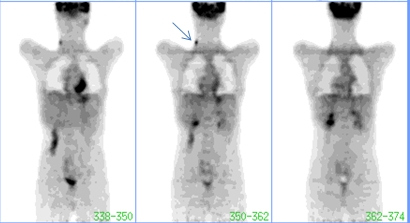

Debido a que la enfermedad había debutado con una adenopatía cervical y la grasa parda dificultaba la interpretación, se coordinó un nuevo estudio para la siguiente semana con estrictas recomendaciones de evitar el frío, agregándose propanolol 40 mg IV y lorazepan 1 mg sublingual.

El segundo procedimiento (fig. 2) demostró claramente la presencia de una adenopatía cervical derecha hipermetabólica, habiendo desaparecido la captación en tejido adiposo pardo.